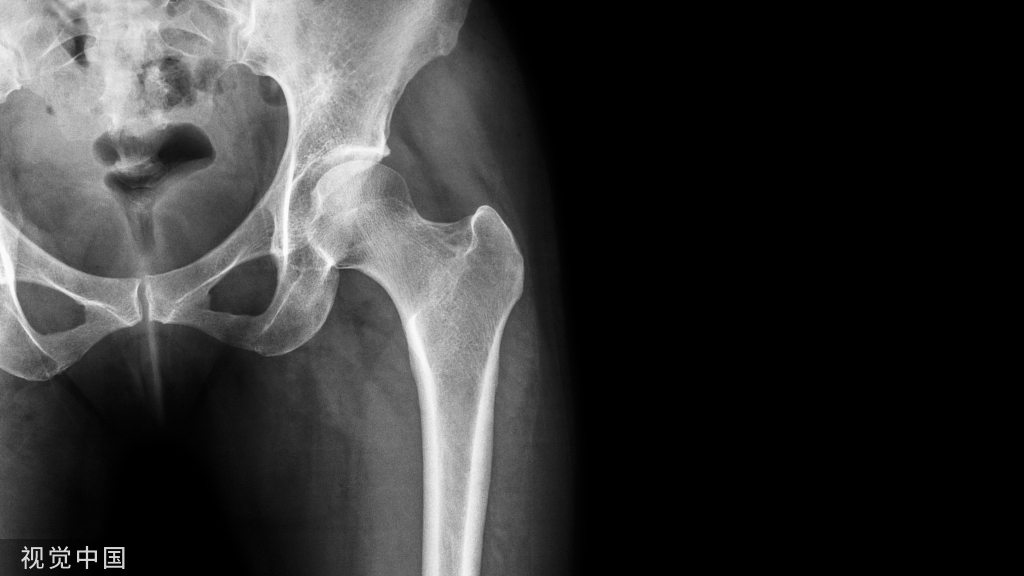

对后Pilon骨折或三踝骨折后踝骨折块的暴露方法主要有3种,一是后外侧入路,该入路可单切口双窗口复位固定外踝和后踝,但该切口对累及内侧的后踝骨折块显露不佳;而是后内侧入路,该入路利于显示内侧骨块,如合并外踝骨折,则需另行外侧切口;三是后内侧与后外侧联合入路,该入路适合于复杂后Pilon骨折,显露清晰,但软组织损伤大。

有学者在临床工作中发现,后Pilon骨折通常合并外踝骨折,且外踝骨折线通常位于下胫腓联合水平,设想通过腓骨骨折间隙,能否显露后踝骨块并达到有效复位?

通过腓骨骨折间隙,撑开器撑开,即可暴露后踝骨折及关节面。清理骨折间隙小骨块,复位塌陷的后踝骨折。